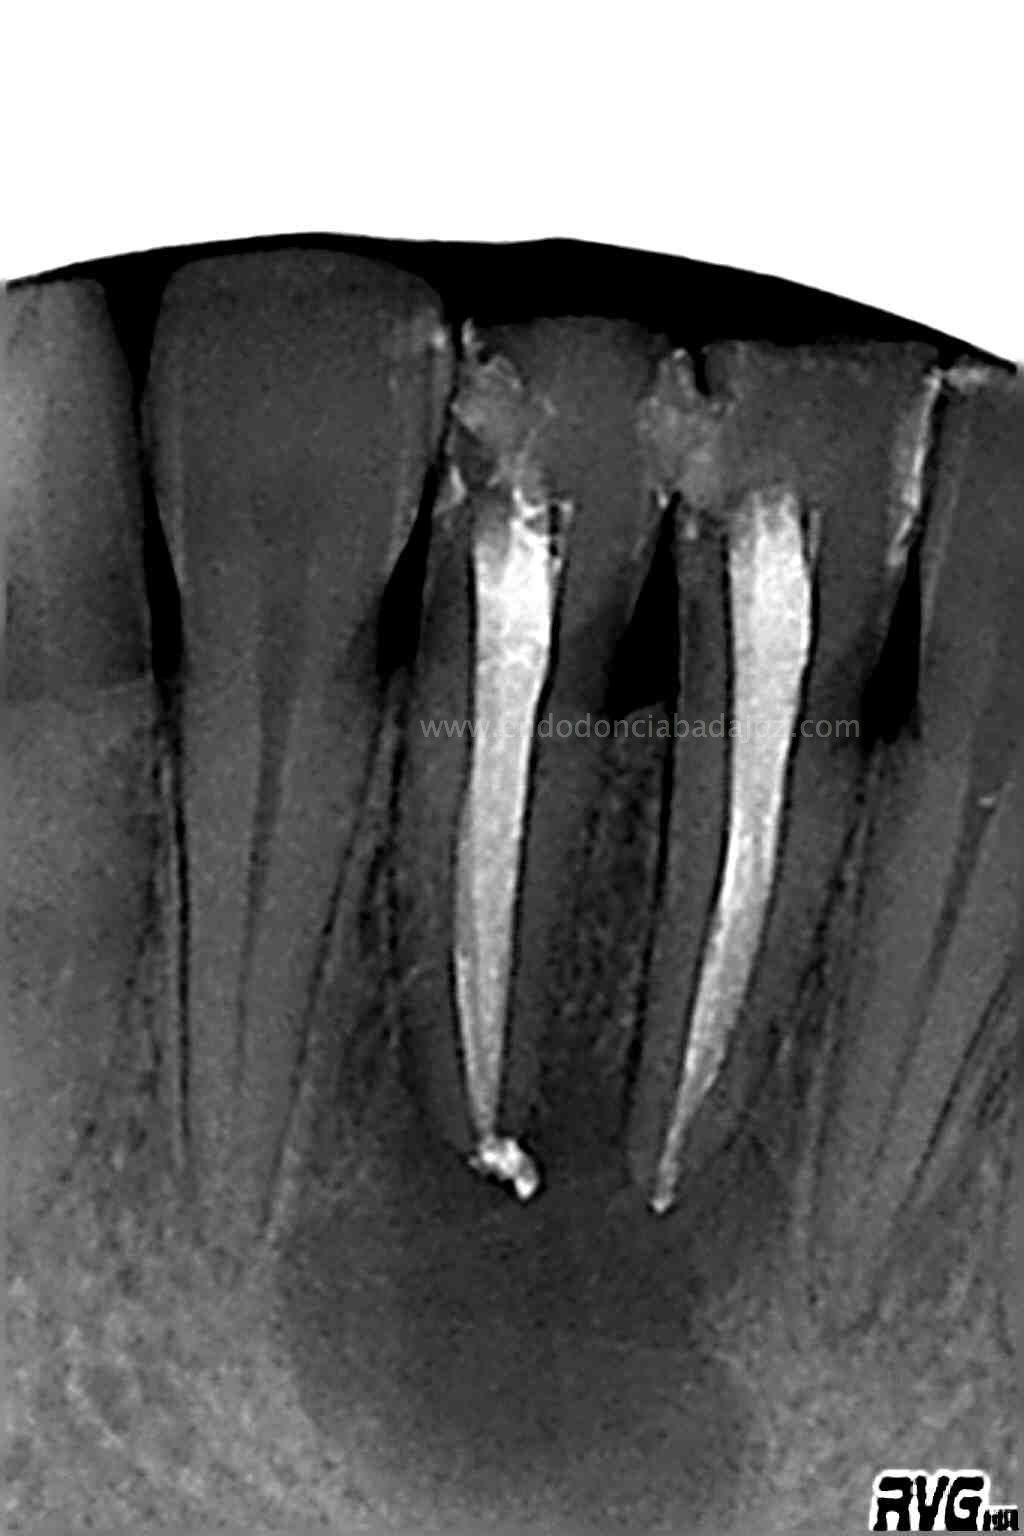

Frente al tratamiento puramente endodóntico, las piezas presentaban vitalidad negativa, fueron tratadas en dos sesiones, rellenando el conducto con Hidróxido de Calcio: